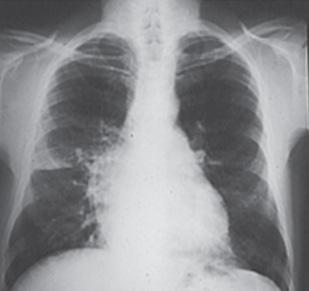

Radiografía: cardiomegalia con hipertensión venosa pulmonar